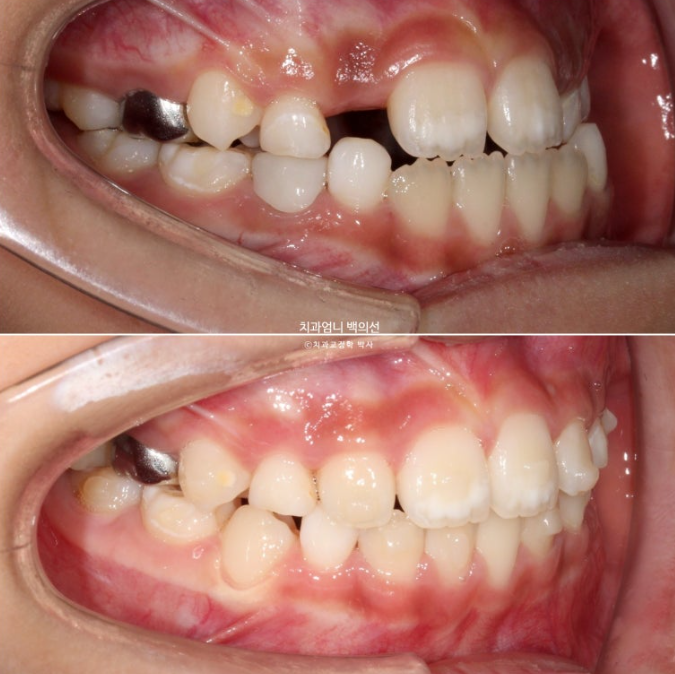

23년 12월 교정치료를 위해 내원한 만 8세 어린이 입니다.

타치과에서 반대교합, 비대칭, 공간이 부족하여 앞니가 못 나오고 있다는 이야기를 듣고 교정을 위해 내원했습니다.

중심선이 많이 어긋나 있으며 파란화살표는 위아래가 거꾸로 물리는 반대교합입니다.

노란색 아래턱의 중심, 흰색이 윗턱의 중심선입니다.

아래턱이 치아중심선 만큼 왼쪽으로 틀어진 비대칭입니다.

유치송곳니끼리 거꾸로 물리는 상태라 이 부분에 교합간섭이 있습니다.

교합간섭에 의해 턱을 한쪽으로 틀어서 물게 되는 경우가 있습니다.

이 경우 악궁확장으로 거꾸로 물리는 부분, 즉 교합간섭을 해결해주면 비대칭이 자연스럽게 좋아지기도 합니다.

윗니가 아랫니를 덮지 못하는 절단교합입니다.

측절치와 송곳니날 자리가 부족해서 악궁확장도 필요한 상황입니다.

인비절라인 퍼스트로 치료에 들어갔고 악궁확장으로 영구치 맹출공간 회복, 공간 분배, 반대교합 해소로 교합간섭 해소에 의한 아래턱 위치 개선으로 비대칭 해결 등을 목표로 치료에 들어갔습니다.